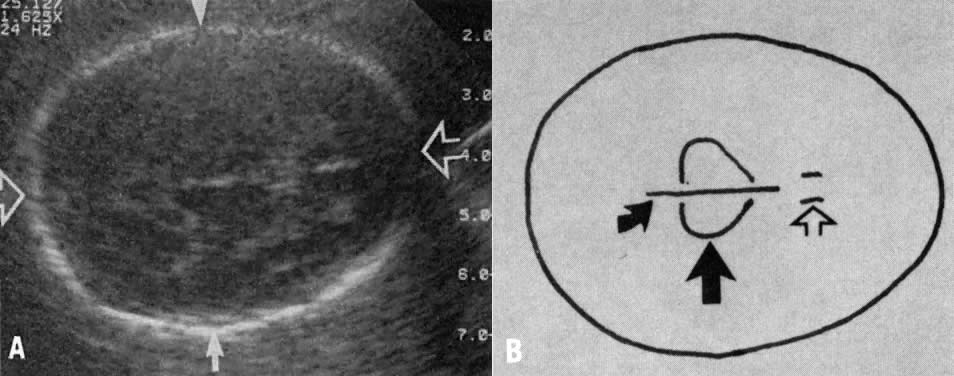

Normality of fetal development should be assessed in relation to specific cephalic and trunk growth parameters. By placing the fetal BPD or HC and AC in specific percentile brackets, nine fetal growth patterns emerge (Fig. 4). A fetus classified into growth patterns three or six (normal BPD but small AC) is at high risk for asymmetric IUGR. By contrast, a fetus classified into growth pattern nine is at high risk for symmetric IUGR.32 The percentile threshold that best delineates states of normal or altered fetal growth, is still undefined. Nonetheless, preliminary observations suggest that by using the 25th percentile as a cut-off point the predictive value of growth patterns three, six, and nine in the diagnosis of IUGR is approximately 80% (see Fig. 4).

Fig. 4. Serial evaluation of biparietal diameter (BPD) or head circumference (HC) and abdominal circumference (AC) permits placement of fetuses in one of nine growth patterns. Those with large HCs and ACs (i.e., growth pattern 1) are at high risk for macrosomia, whereas those with large or normal head size but with small ACs (i.e., growth patterns 3 and 6) are at high risk for asymmetric growth retardation. Fetuses placed in growth pattern 9 are at high risk for symmetric growth retardation.(Sabbagha RE: Intrauterine growth retardation. In Sabbagha RE [ed]: Diagnostic Ultrasound Applied to Obstetrics and Gynecology, 2nd ed, p 120. Philadelphia, JB Lippincott, 1987)